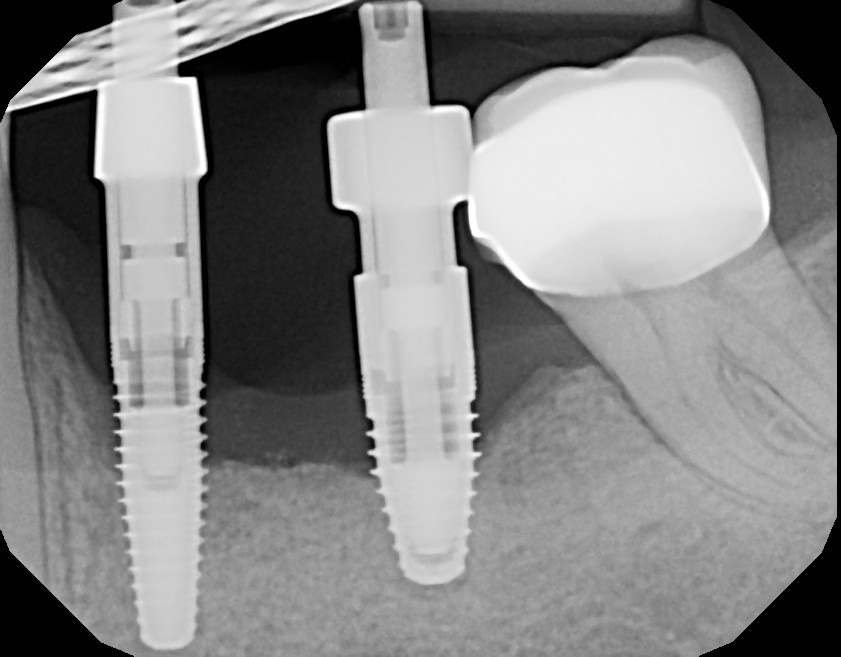

The implant platform can also have different shapes. It can have an internal or external platform with the abutment. The original Brånemark system had an external connection. The internal connection platform is the most preferred method used now in dental practices (Figure 11 through Figure 13).

After 4 to 6 months of tissue healing and osseointegration, the final restoration is fabricated. An impression is obtained, either at implant level or at the abutment level, to fabricate the final crown. The implant-level impression records the implant position and requires precision. An impression coping is screwed onto the implant to be transferred into the impression. The copings are utilized for a closed- or open-tray technique. The closed-tray technique is used mostly with one implant, and the open-tray technique is used more frequently for multiple implants, when different implant angles exist (Figure 31 and Figure 32). With either technique, the impression material most often recommended is polyether.38 Bite registration, shade selection, and opposing models are collected in the same manner as crown-and-bridge cases.